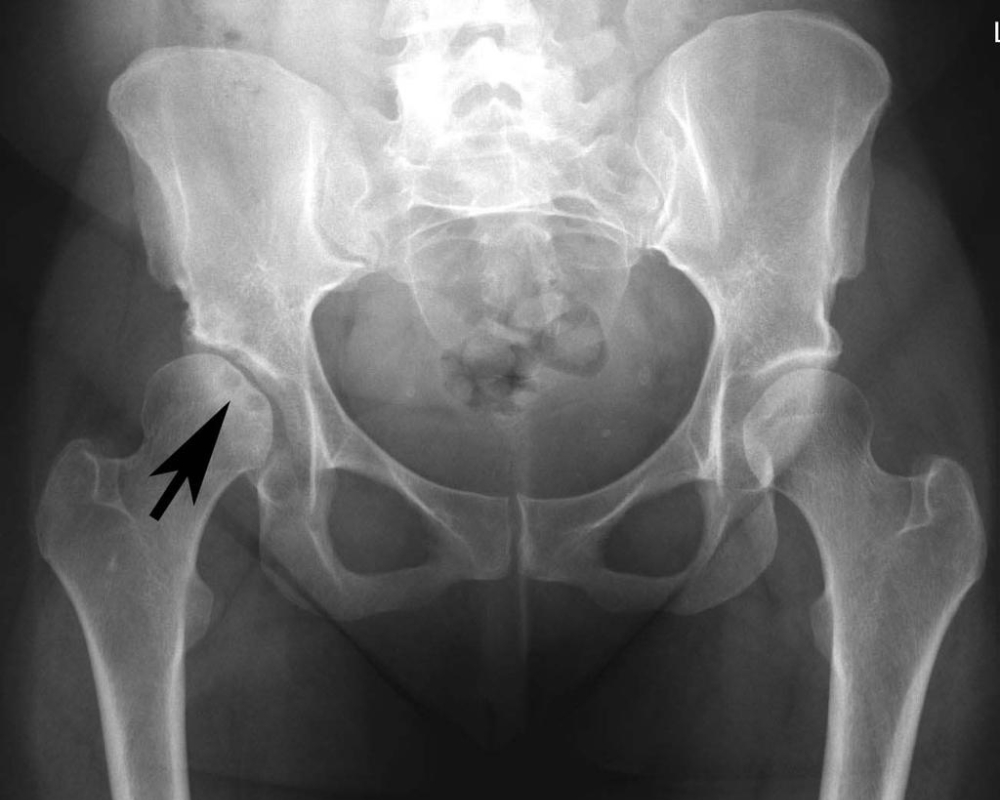

Các phương pháp chẩn đoán thoái hóa khớp háng

Xét nghiệm hình ảnh X-quang được sử dụng để xem xét cấu trúc xương và xác định mức độ mất mát sụn khớp. Nó có thể cho thấy các dấu hiệu của thoái hóa như giảm mật độ xương, tạo hình xương bất thường và tăng kích thước các xương xung quanh khớp.

Xét nghiệm hình ảnh Chụp CT và MRI. Cả hai phương pháp này cung cấp hình ảnh chi tiết về cấu trúc xương, sụn và mô mềm xung quanh khớp. Chúng có thể giúp xác định mức độ tổn thương và viêm nhiễm trong khớp.